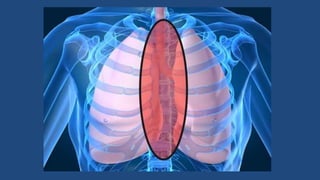

Mediastinite

• Processo infeccioso toma

uma via descendente no

pescoço, através dos

espaços látero-faríngeo,

retroferíngeo, alcançando a

bainha carotídea e chegam

ao tórax, na região do

mediastino

• Sinais e sintomas: dispnéia

intensa, dor torácica, febre

alta não-remissível

• Complicações: septicemia,

abscesso

mediastinal,empiema,efusã

o pleural, pericardite, óbito

(40% de mortalidade)

• Tratamento: além de

remoção da causa,

antibióticos e.v.,

traqueostomia, deve ser

feita a drenagem do tórax.

Mediastinite • Processo infecciosotoma uma via descendente no pescoço, através dos espaços látero-faríngeo, retroferíngeo, alcançando a bainha carotídea e chegam ao tórax, na região do mediastino • Sinais e sintomas: dispnéia intensa, dor torácica, febre alta não-remissível • Complicações: septicemia, abscesso mediastinal,empiema,efusã o pleural, pericardite, óbito (40% de mortalidade) • Tratamento: além de remoção da causa, antibióticos e.v., traqueostomia, deve ser feita a drenagem do tórax.